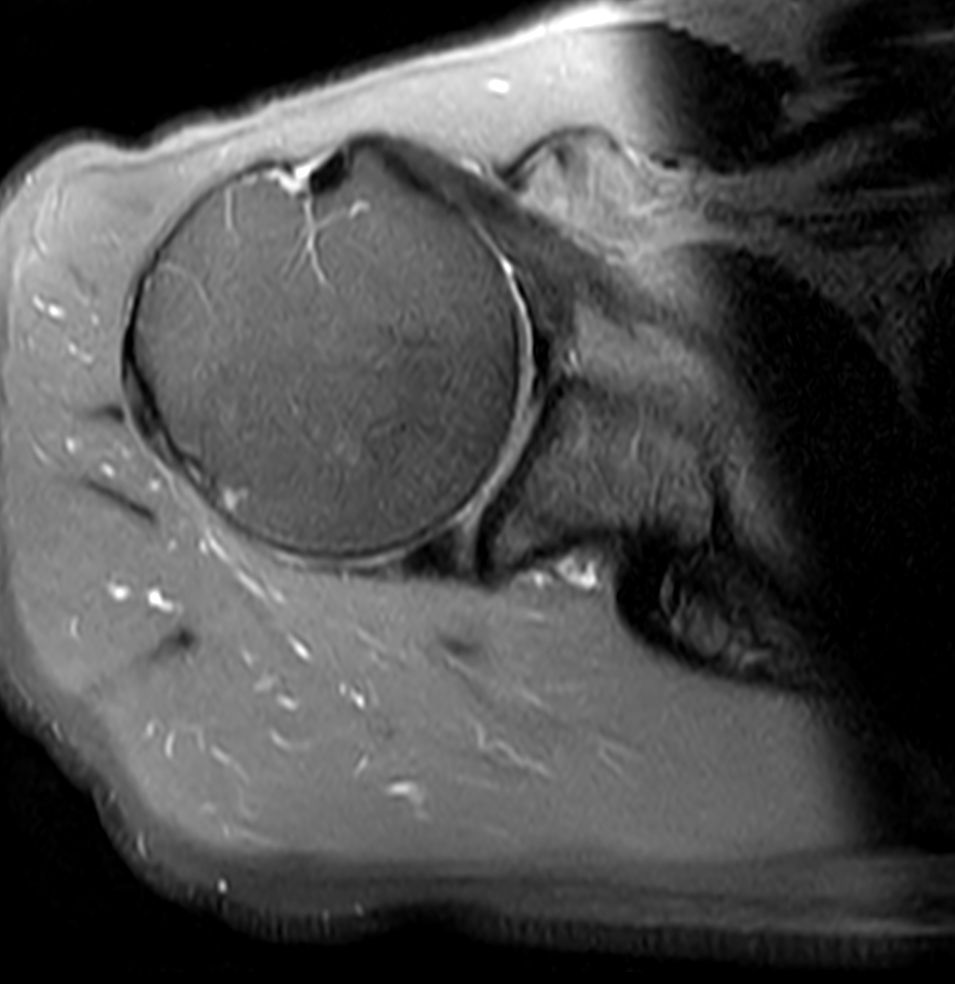

Axial PDw TSE FatSat